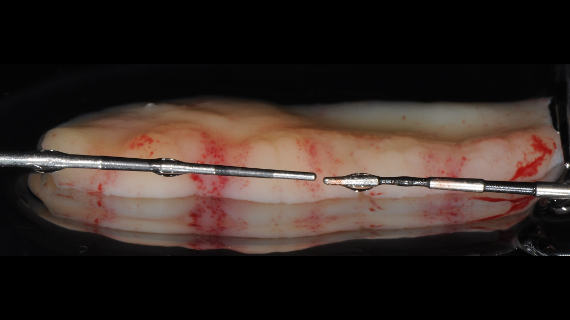

Neste webinar será abordado o diagnóstico e o tratamento das deficiências nos tecidos moles à volta de dentes e implantes. Serão abordadas as técnicas mais atuais, ilustradas com diversos casos clínicos. Serão também discutidos os fatores chave para um tratamento previsível deste tipo de situações.